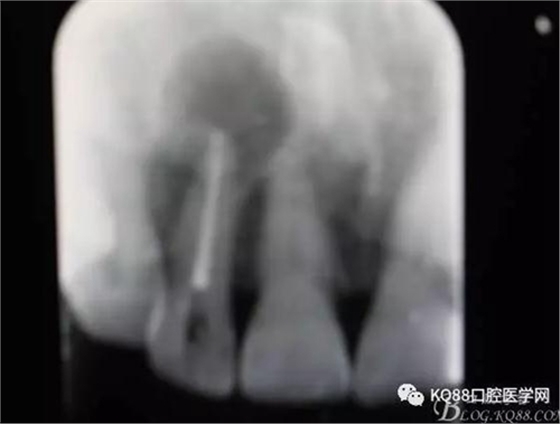

圖2. 12牙齒在我院進(jìn)行熱牙膠根管充填+樹(shù)脂充填。

一個(gè)月后患者復(fù)查: 唇側(cè)觀:11根尖區(qū)粘膜有一膿瘺,捫診溢膿,牙冠成灰褐色。根管治療無(wú)法治愈根尖病變,建議根管外科治療,患者同意手術(shù)。